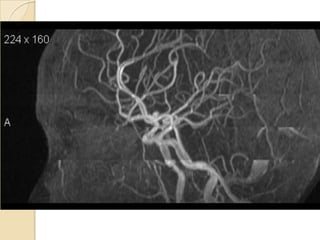

Arteries of the brain (lateral view) - MRA

1. Anterior cerebral artery

2. Anterior communicating artery

3. Basilar artery

4. branches (in insula) of middle cerebral artery

5. Cavernous portion of internal carotid artery

6. Cervical portion of internal carotid artery

7. Genu of middle cerebral artery

8. Intracranial (supraclinoid) internal carotid artery

9. Middle cerebral artery

10. Ophthalmic artery

11. Petrous portion of internal carotid artery

12. Posterior cerebral artery

13. Posterior cerebral artery in ambient cistern

14. posterior cerebral artery in interpeduncular

cistern

15. Posterior communicating artery

16. Posterior inf cerebellar artery.

17. Quadrigeminal portion of posterior cerebral

artery

18. Superior cerebellar artery

19. Vertebral artery